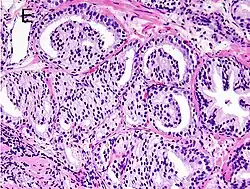

Cytological differences between normal prostate and neoplastic glands are evident in changes to the typical two cell layers of the gland. In prostatic adenocarcinoma, the basal (bottom, usually cuboidal type) cell layer is lost, with only the top layer (usually columnar to pseudostratified) remaining.

Gleason 3 is a clearly infiltrative neoplasm, with extension into adjacent healthy prostate tissue. The glands alternate in size and shape, and are often long/angular. They are usually small/micro-glandular in comparison to Gleason 1 or 2 grades. However, some may be medium to large in size. The small glands of Gleason 3, in comparison to the small and poorly defined glands of pattern 4, are distinct glandular units. Mentally you could draw a circle around each of the glandular units in Gleason 3.[4][7]

Gleason pattern 4 glands are no longer single/separated glands like those seen in patterns 1–3. They look fused together, difficult to distinguish, with rare lumen formation vs Gleason 1–3 which usually all have open lumens (spaces) within the glands, or can be cribriform-(resembling the cribriform plate/similar to a sieve: an item with many perforations). Fused glands are chains, nests, or groups of glands that are no longer entirely separated by stroma-(connective tissue that normally separates individual glands in this case). Fused glands contain occasional stroma giving the appearance of "partial" separation of the glands. Due to this partial separation, fused glands sometimes have a scalloped (think looking at a slice of bread with bite taken out of it) appearance at their edges.[4][7]